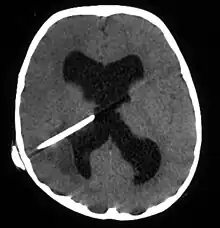

Brain abscess in a person with a CSF shunt. The abscess is the darker gray region in the lower left of the image (corresponding to the right parietal lobe). The lateral ventricles are visible in black in the center of the brain, adjacent to the abscess.[1]

Brain abscess (or cerebral abscess) is an abscess within the brain tissue caused by inflammation and collection of infected material coming from local (ear infection, dental abscess, infection of paranasal sinuses, infection of the mastoid air cells of the temporal bone, epidural abscess) or remote (lung, heart, kidney etc.) infectious sources. The infection may also be introduced through a skull fracture following a head trauma or surgical procedures. Brain abscess is usually associated with congenital heart disease in young children. It may occur at any age but is most frequent in the third decade of life.